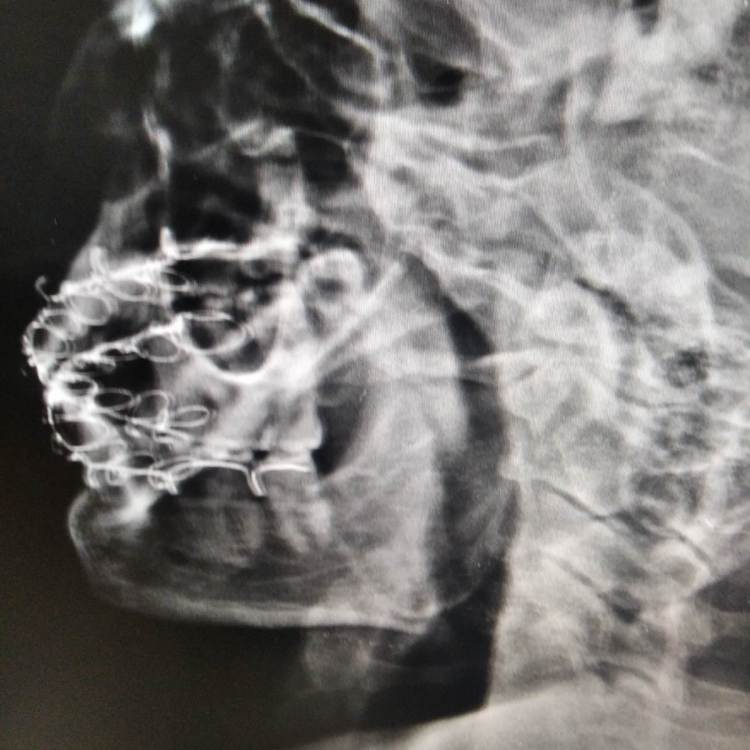

Russ Опубликовано 16 августа, 2022 Поделиться Опубликовано 16 августа, 2022 Доброго времени суток, Уважаемые специалисты и посетители форума. Очень нужна Ваша помощь. 6 недель назад получил закрытый перелом челюсти справа со смещением. Зуб мудрости удалили, зашинировали, ожидании операции провел неделю в стационаре , но был выписан, сказали "так сростется". Загрузил фото рентгена (10 дней после наложения шин) и фото КТ (6 недель). Бежать заново ломать, пока не схватилось до конца все? Заранее спасибо. Ссылка на комментарий

kramer Опубликовано 17 августа, 2022 Поделиться Опубликовано 17 августа, 2022 Отломки явно не на своем месте. Надо делать остеосинтез. 1 1 2 Ссылка на комментарий

Doc Опубликовано 18 августа, 2022 Поделиться Опубликовано 18 августа, 2022 Если сейчас еще можно решить вопрос правильным сопоставлением отломков, то потом могут начаться проблемы с суставом, к примеру, которые вообще никак не решить будет. Так что лучше сейчас. 1 Ссылка на комментарий